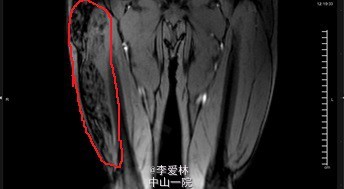

患者男,44岁,主因“右大腿血管瘤栓塞术后10年,右大腿酸痛2年”入院。患者10年前因“右侧大腿血管瘤”于外院行栓塞术,术后规律随访。2年前起感右大腿酸胀伴疼痛,无发热寒战,无肢体红肿,无活动受限。

右侧大腿外侧可及直径约8cm肿物,质偏硬,边界不清。右大腿可见不规则疤痕。右侧大腿较左侧粗。双上肢、左下肢、右小腿未见明显异常。双侧肱动脉、桡动脉、股动脉、足背动脉搏动佳。我院大腿MR:右大腿软组织病变,大小约78×50mm,累及长度约25mm,考虑蔓状血管瘤,病灶由股浅动脉分支供血,下部呈血管湖改变。